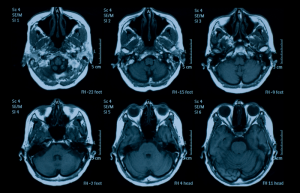

Neuro MRI (Brain & Spine) 🧠

New protocols: DWI, SWI, ASL, fMRI

Updated diagnosis: MS, stroke, tumors

Detecting subtle lesions with high-resolution imaging

DTI and tractography advancements in 2024

This section is designed to improve accuracy in complex neurological cases and support more confident decision-making and reporting, especially for subtle findings. ⚡️